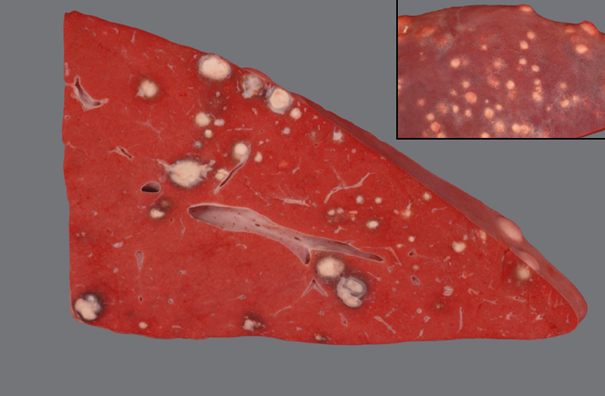

Rind, Niere: Hochgradige chronische diffuse Amyloidose der Niere (Amyloidnephrose)

Beschreibung:

Nierenrinde hellbeige

Oberflächefeingranuliert, speckig

die Renculi erscheinen prominent

derbe Konsistenz

Hintergrundwissen/ Pathogenese/Ätiologie

- Amyloid ist ein fibrilläres Protein, in dem die β-Faltblattstruktur dominiert vermehrter Anfall durch

gesteigerte Synthese oder unvollständige Proteolyse

- Amyloidnephosen v.a. bei Rind, Hund, Katze

AA Amyloid:

- In der Niere meist reaktive systemische Amyloidose: chronischen Entzündungsprozessen ->

gesteigerte Synthese von Serum-Amyloid-A-Protein (Akute-Phase-Protein) durch Hepatozyten ->

Abgabe ins Blut sekundäre Ablagerung von AA-Amyloid vor allem in den Glomeruli

- Familiäre Amyloidose (z.B. Shar-Pei, Abessinerkatze)

AL-Amyloid:

- Selten, z.B. beim Multiplen Myelom

- Beeinträchtigung der glomerulären Filtration durch vermehrte Durchlässigkeit -> Proteinurie, nephrotisches Syndrom

- Differentialdiagnose: Lymphom